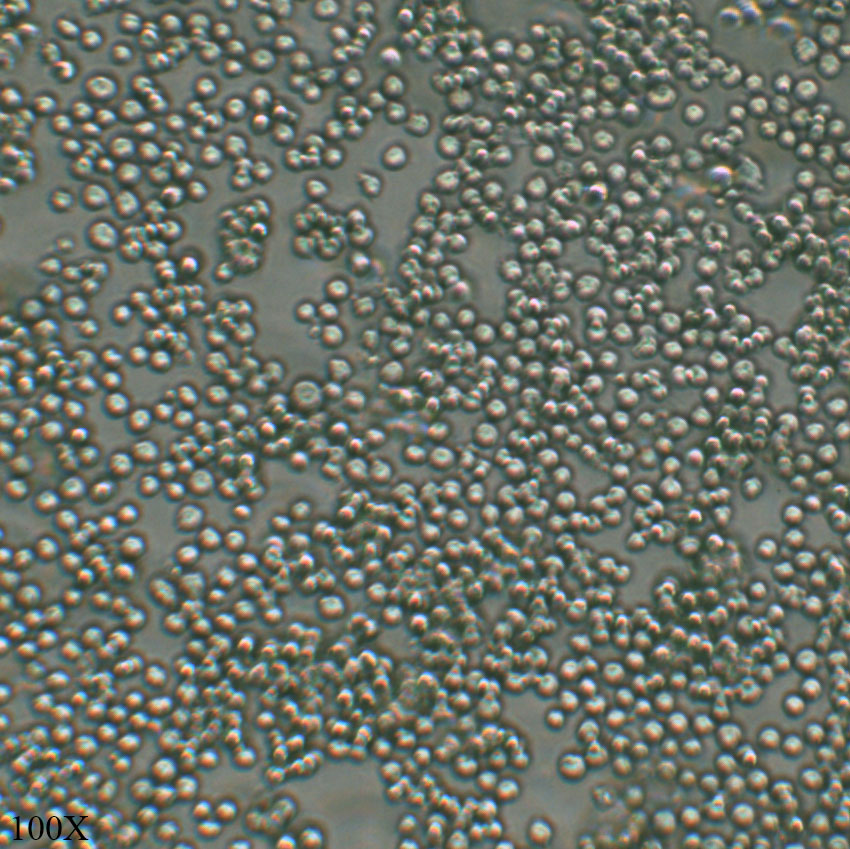

形态特征 淋巴母细胞样

生长特征 悬浮

传代比例 1:3传代;维持细胞密度在1*10^5-1*10^6cells/ml(培养面积比)